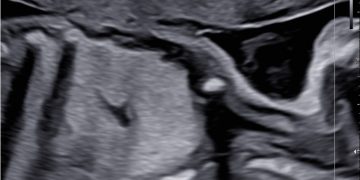

Casi del Mese di Dicembre 2024

Cari soci, finalmente on line le soluzioni dei casi del mese di Dicembre. Grazie a Sara Zullino e Mara Albanese!! Caso 1 - video [pdf-embedder url="https://www.sieog.it/wp-content/uploads/2024/12/Casodelmese_Dicembre2024caso-risposte_gineco.pdf"...